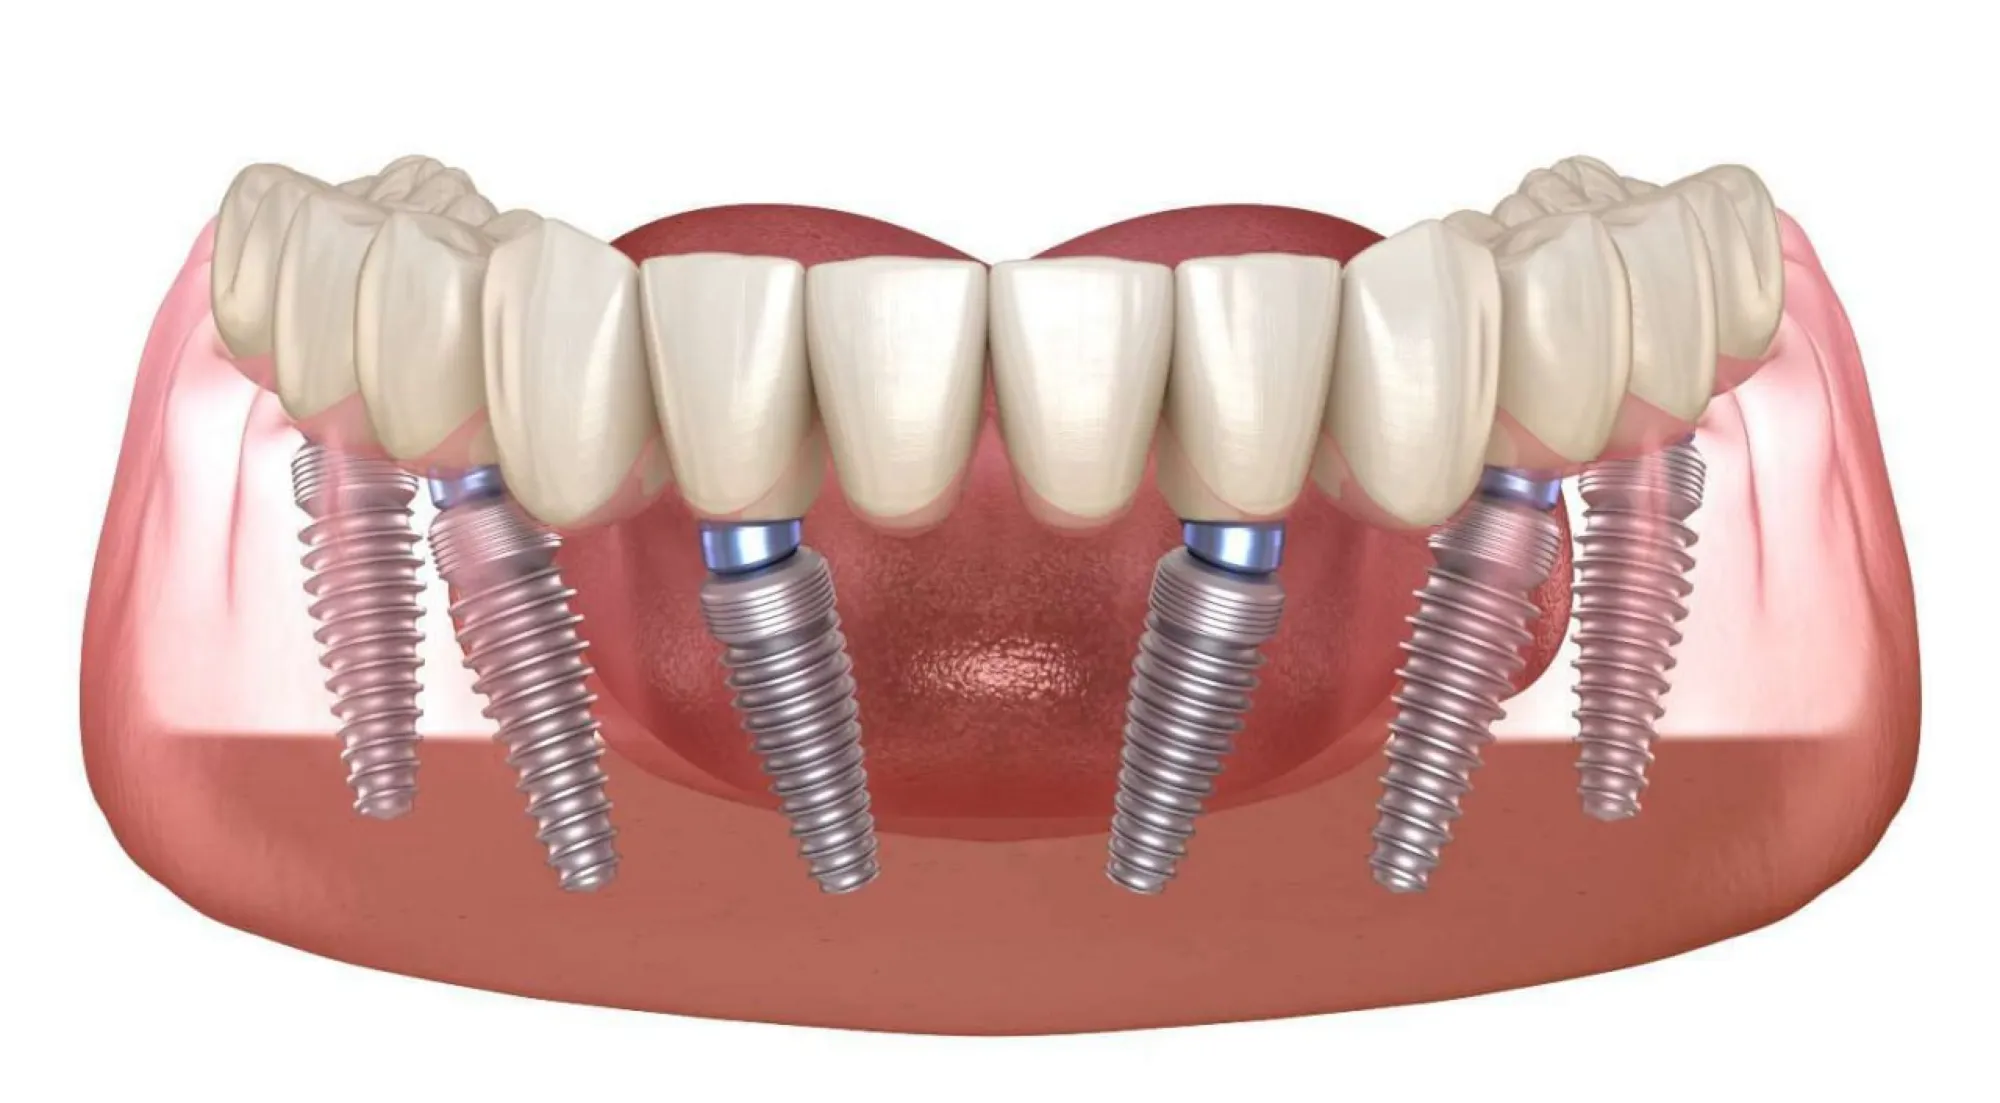

Технология All-on-6 разработана для пациентов, страдающих полной или почти полной адентией в жевательных отделах челюсти и атрофией костной ткани. Основная идея заключается в установке шести дентальных имплантатов: четыре в передней части и два под углом от 25 до 45 градусов в задней части челюсти. Сразу после этой процедуры производится немедленное протезирование зубов несъемным протезом.

В рамках одного визита удаляются поврежденные зубы, вживляются шесть имплантатов, устанавливаются абатменты. После этого делаются слепки для временного протезирования, который изготавливается и устанавливается в тот же день, обычно через несколько часов после операции.